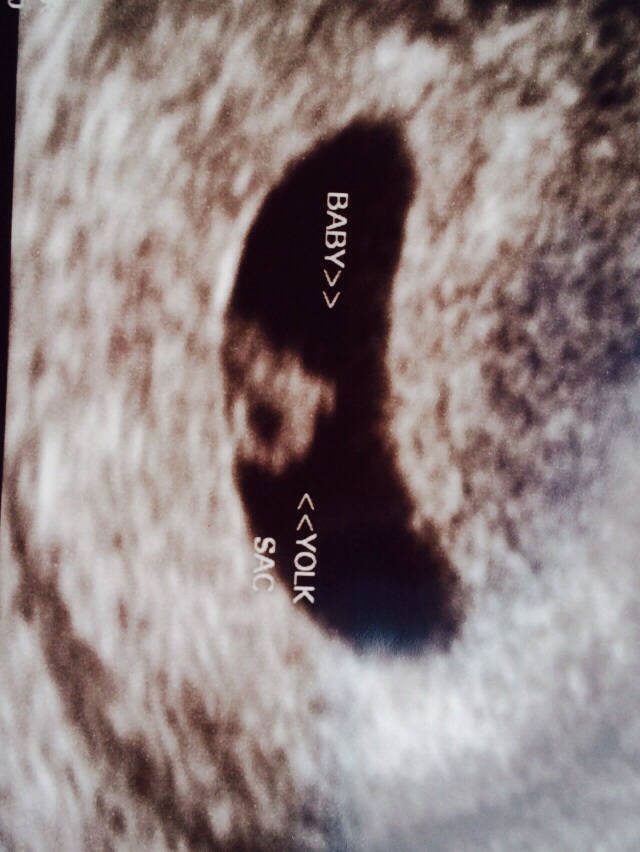

Wonder if it a boy and girl. I hear if heart rate is over 140 it's a girl and under 140 it's a boy @mswatters

Both my twins heart rates were in the 160s and they were boys :)